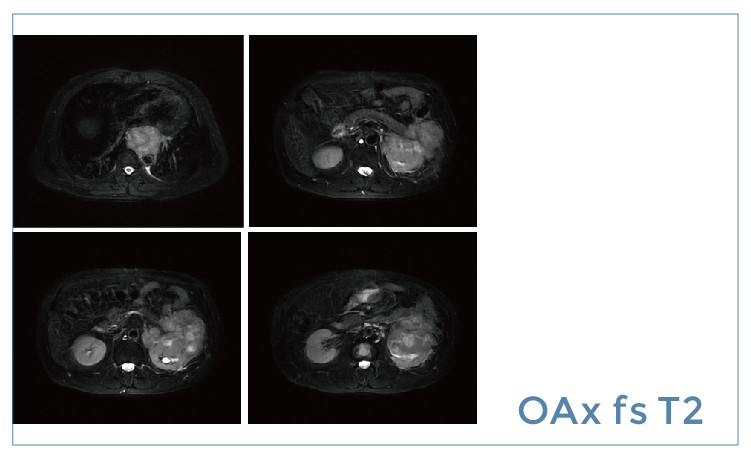

【朗润影像档案】20190426磁共振影像病例结果讨论